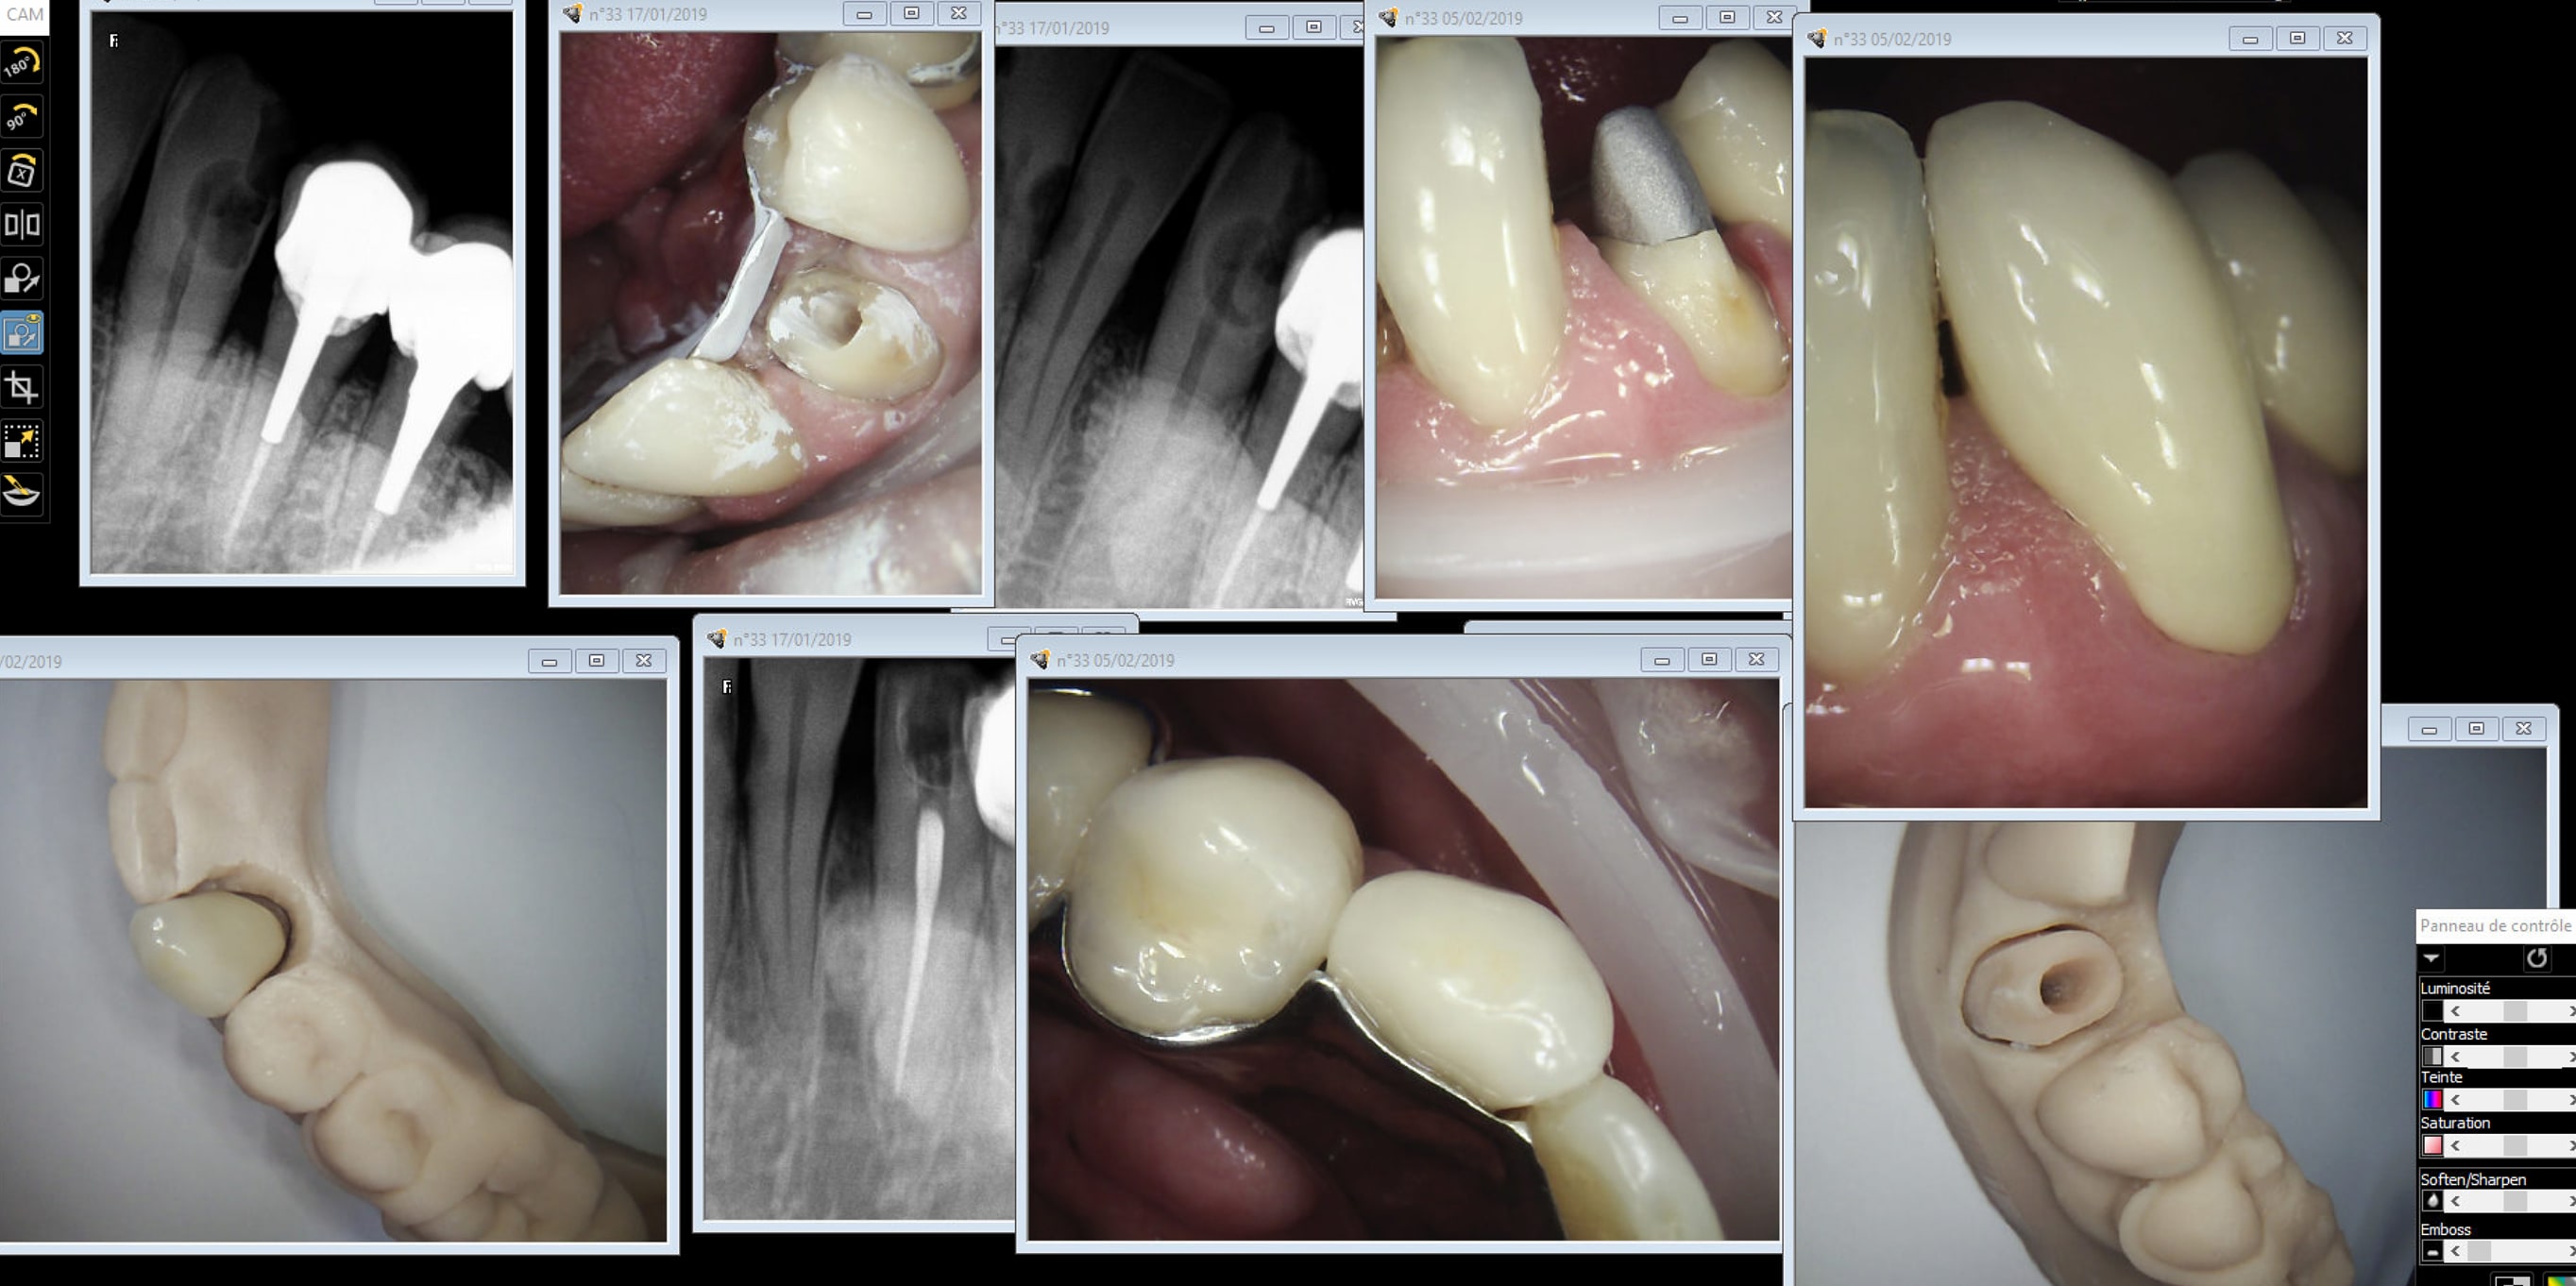

Capture d écran 2019 02 04 22.15 - Eugenol

Capture d écran 2019 02 05 14.53 - Eugenol